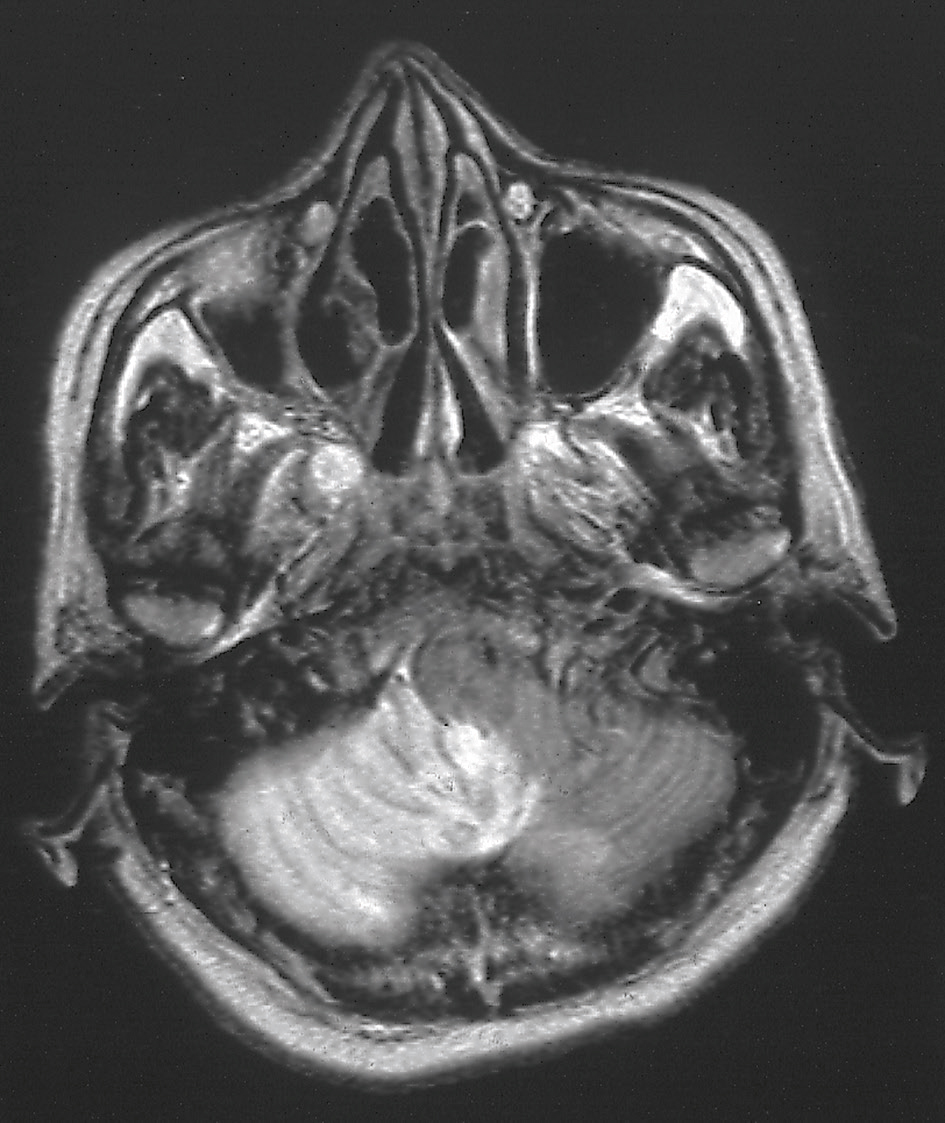

Au moindre doute sur cette étiologie, une prise en charge de type accident vasculaire constitué doit être organisée, notamment une mutation en unité neurovasculaire si les délais de la thrombolyse/thrombectomie sont respectés. Une IRM est plus performante que le scanner cérébral pour mettre en évidence la lésion ischémique (fig. 14.6).

IRM en séquence T2 montrant une lésion ischémique en hypersignal dans le territoire de l’artère cérébelleuse postéro-inférieure gauche. Le patient présente un syndrome vestibulaire aigu isolé.

L'image montre une IRM en séquence T2 d'une coupe axiale du cerveau. On observe une lésion ischémique en hypersignal dans le territoire de l’artère cérébelleuse postéro-inférieure gauche. Cette lésion apparaît plus brillante que les tissus environnants, indiquant une zone de dommage ou de mort cellulaire due à une interruption de l'apport sanguin. Les séquences T2 sont particulièrement utiles pour détecter les anomalies de l'eau dans les tissus, ce qui permet de visualiser les zones d'œdème ou de nécrose. Cette lésion ischémique dans le territoire de l’artère cérébelleuse postéro-inférieure gauche est importante à identifier, car elle peut entraîner des symptômes neurologiques significatifs en raison de son emplacement dans le cerveau. Le cervelet joue un rôle crucial dans la coordination des mouvements, l'équilibre et la posture. Une lésion dans cette région peut donc affecter ces fonctions et entraîner des symptômes tels que des troubles de l'équilibre, des vertiges, des nausées et des difficultés de coordination. L'IRM en séquence T2 permet de visualiser avec précision la zone ischémique, fournissant des informations essentielles pour le diagnostic et la gestion des accidents vasculaires cérébraux. La détection précoce de ces lésions est cruciale pour améliorer les résultats cliniques et offrir des options de traitement appropriées aux patients. En résumé, l'image montre une lésion ischémique en hypersignal dans le territoire de l’artère cérébelleuse postéro-inférieure gauche, mettant en évidence une zone de dommage cellulaire due à une interruption de l'apport sanguin.